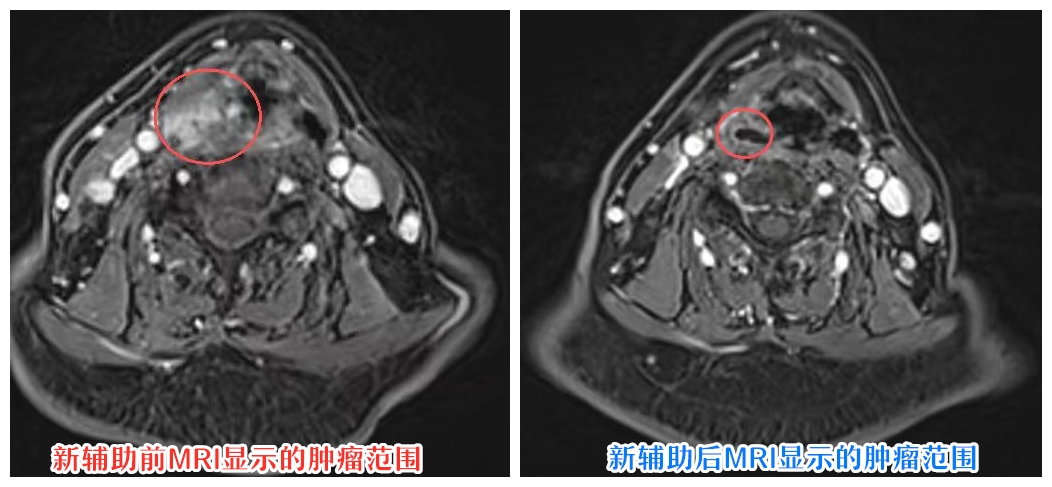

团队决定先采用新辅助化疗,让肿瘤“缩水”。两个周期后,陈某下咽及颈部的肿块明显变小,吞咽也顺畅了些。随后,医生通过精准定位,对缩小后的肿瘤进行完整切除,成功保住了喉,而非全喉切除。术后复查时,陈某不仅肿瘤病灶清除干净,还能清晰地和医生交流:“没想到我还能正常说话,太感谢李主任团队所有医护人员了!”

如今,重庆市人民医院耳鼻咽喉头颈外科创新建立的“局部晚期头颈鳞癌综合治疗技术”,改变了这一局面。该技术以多学科协作(MDT)为基石,将放疗、化疗、手术“三位一体”深度融合,形成“一体化作战”模式:以手术实现肿瘤根治的核心,先通过新辅助化疗,让原本“庞大”的肿瘤显著缩小,实现“肿瘤降级”;再根据肿瘤缩小后的范围,采用精准的局部切除手术,避免过度损伤;最后结合精准放疗巩固疗效,降低复发风险。